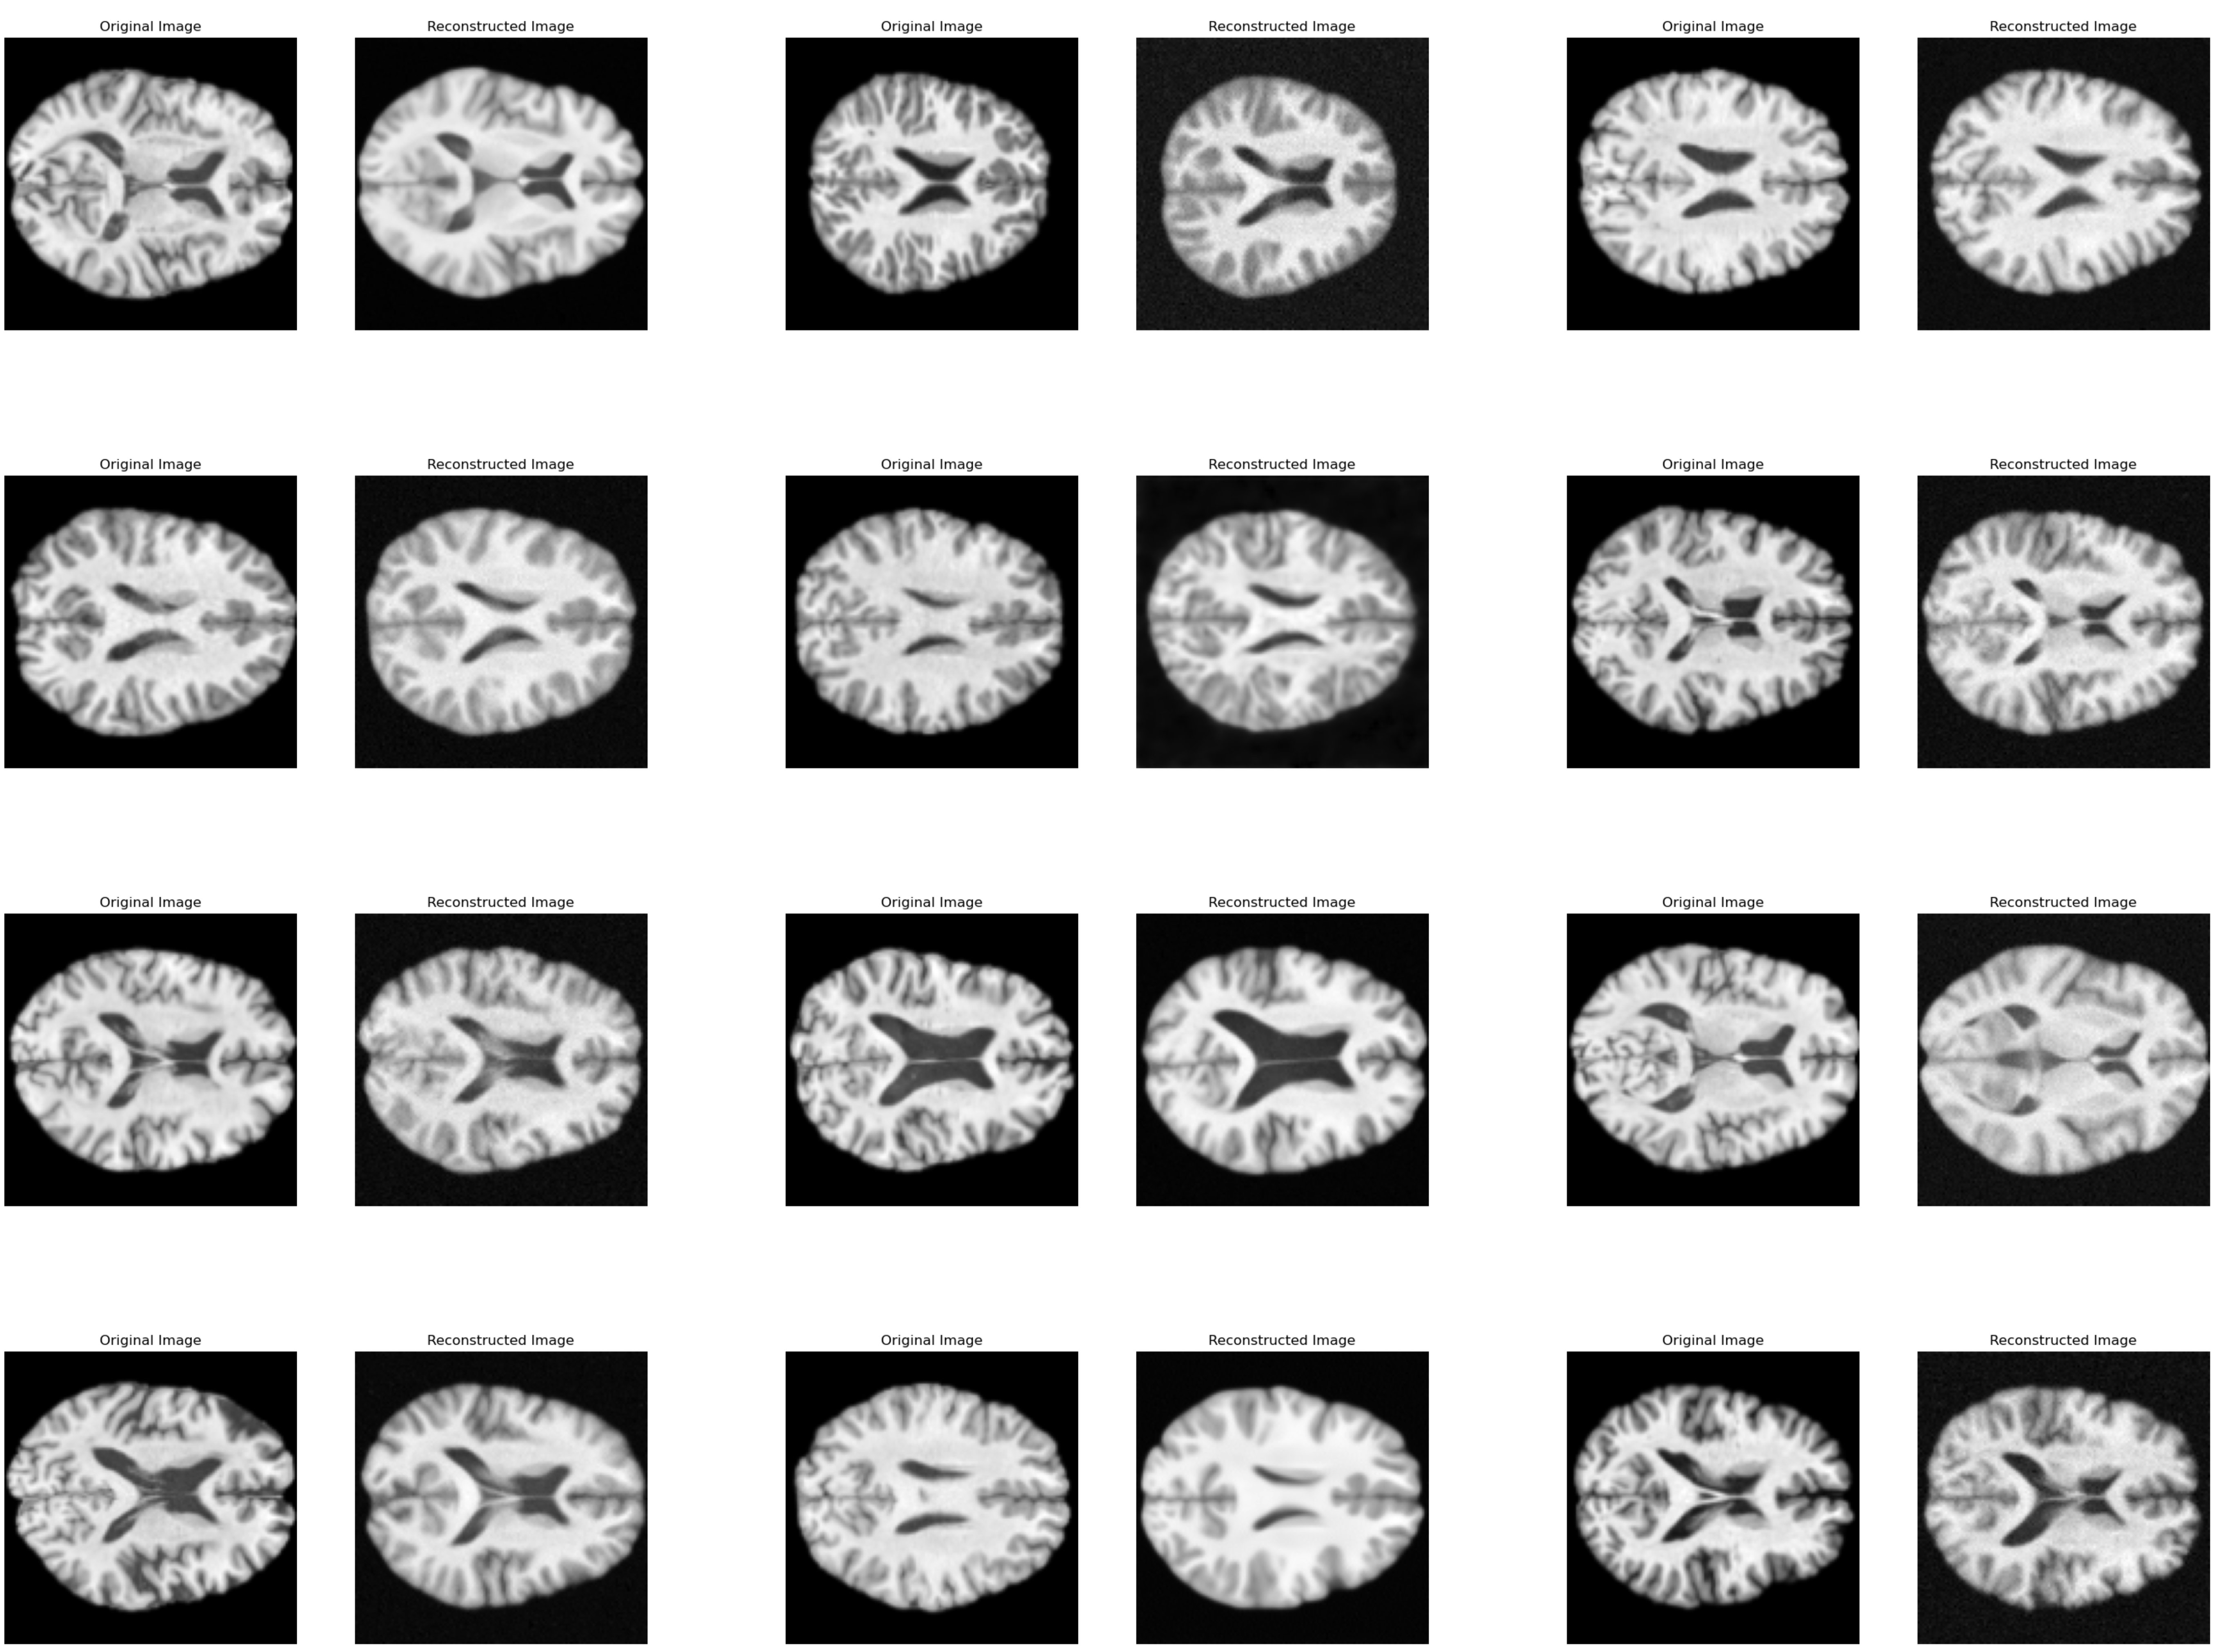

Refer to caption

Figure 4: Image Reconstructions. The images on the left columns are the original image, and the images on the right columns are their reconstructed version.